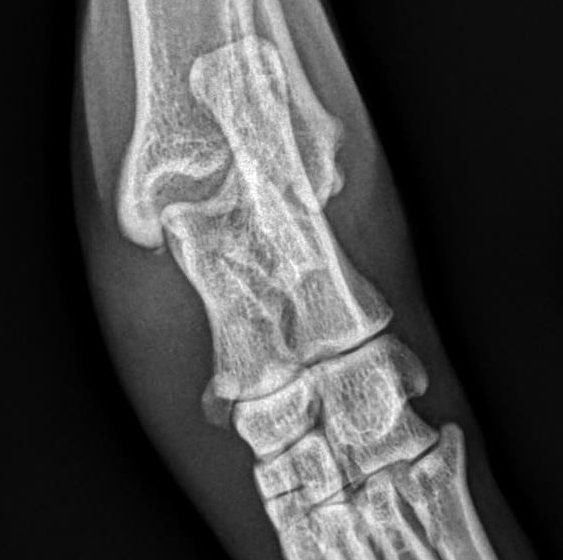

Casos clínicos: paciente, Tobby.

“Toby” es un cachorro de Ratonero Valenciano de 4 meses de edad y un peso de 5 kg. Tras un pequeño accidente doméstico en el